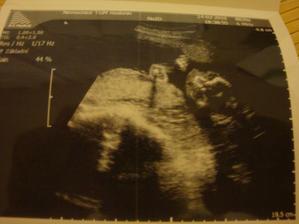

ladena

30. jún 2009

Čakáme bociana v auguste 2010